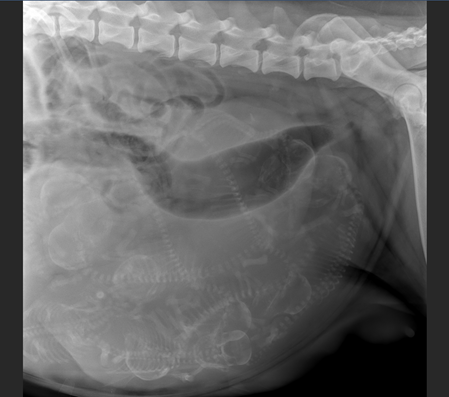

...das Wunder beim Röntgen

Am 05.Juni 2025 erblicken unsere E-chens das Licht der Welt

4 Mädchen und 5 Jungs + ein Sternenmädchen